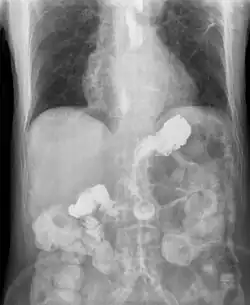

This is commonly due to transient or permanent changes in the barrier between the esophagus and the stomach. This can be due to incompetence of the lower esophageal sphincter, transient lower esophageal sphincter relaxation, impaired expulsion of gastric reflux from the esophagus, or a hiatus hernia. If the reflux reaches the throat, it is called laryngopharyngeal reflux disease.